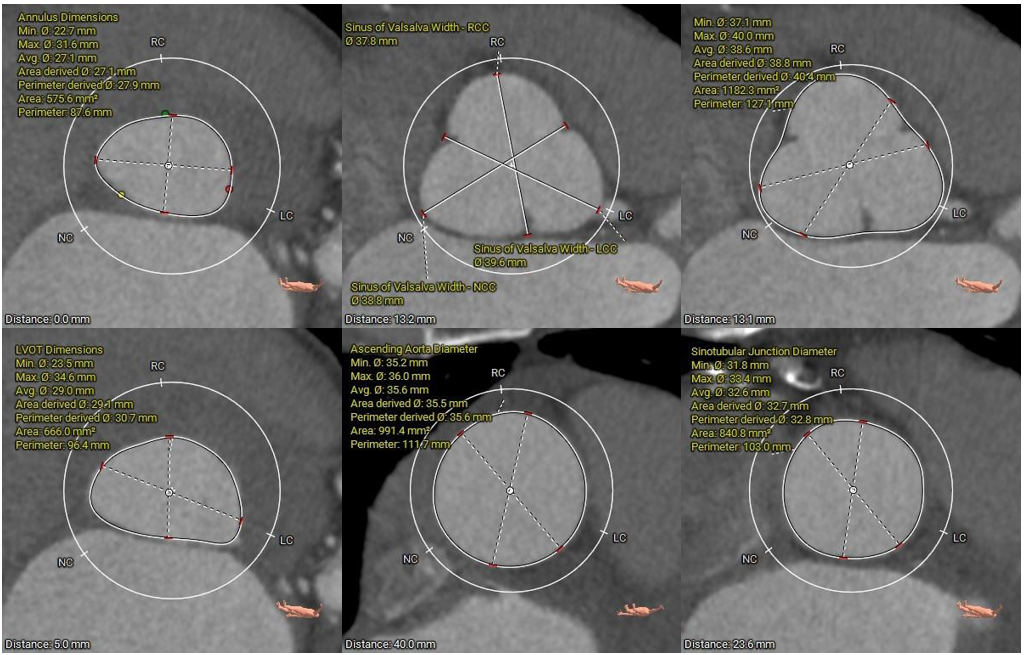

术前CT评估要点

• 三叶式主动脉瓣,瓣叶增厚伴中重度钙化,钙化主要分布于左冠及无冠瓣叶边缘处,左右窦间可见钙化粘连;左室流出道呈敞口型;

• 左右冠开口高度尚可,切线位测量未见冗长瓣叶;

• 瓦氏窦、窦管交界、升主动脉内径尚可;

• 左室腔内径扩大,心室壁稍偏薄,心尖部心肌菲薄;

• 瓣环平面与水平面夹角为37°;主动脉弓距及夹角尚可;

主动脉根部测量

瓣上结构测量及钙化积分